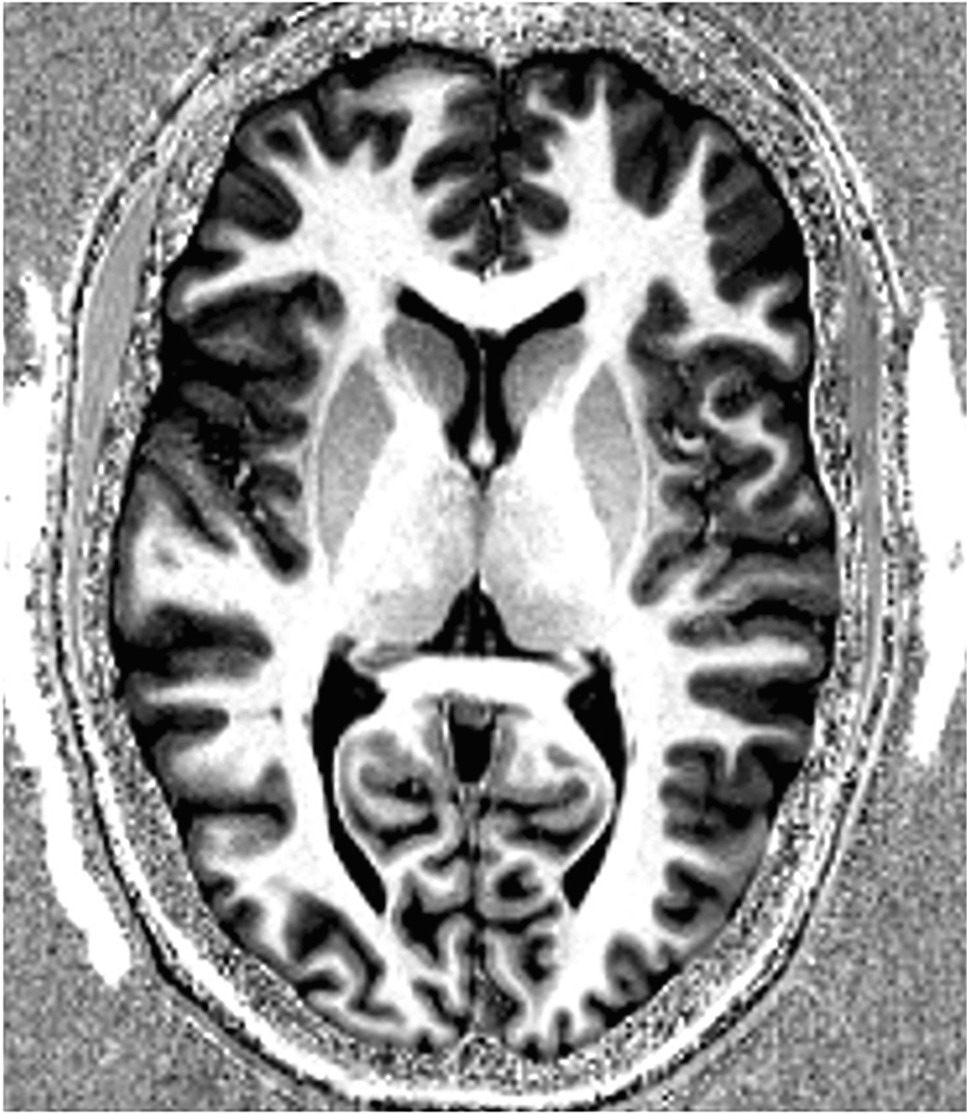

Development of a clinically applicable 7 T and 9.4 T MRI scan protocol for detection of structural abnormalities is part of this study. We created a format for a proposed UHF scan protocol (see Table 2). All sequences will acquire images of the whole brain. This scan protocol allows for the use of normative control data, acquired by Haast et al. [30]. Two dielectric CaTiO3 pads with demineralized water are used to improve the inhomogeneous MRI signal in the temporal lobes. As a preparation, we scanned some controls at 7 T to assess image quality (see Figs. 2 and 3).

Fig. 2

7 T 3D T1-MP2RAGE axial image of a test subject’s cerebrum with an isotropic voxel size of 0.7 mm. The di-electric pads can be seen on both sides